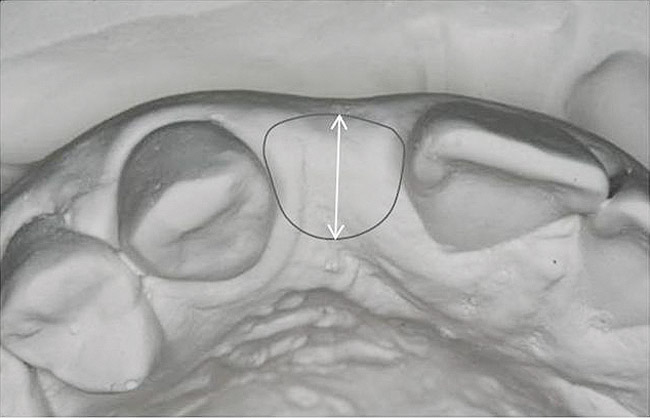

Figure 13   Exploiting study casts for planning single-tooth implant placement and restoration: Mounted study casts permit an estimation of available bone volume (Fig 13); measure the bound edentulous space inter-tooth dimensions (Fig 14); measure the available inter-arch dimension (restorative space) (Fig 15); and evaluate alveolar ridge/tooth relationships (distance from zenith represented by plastic stent to ridge crest) (Fig 16).

Figure 13

Figure 14   Exploiting study casts for planning single-tooth implant placement and restoration: Mounted study casts permit an estimation of available bone volume (Fig 13); measure the bound edentulous space inter-tooth dimensions (Fig 14); measure the available inter-arch dimension (restorative space) (Fig 15); and evaluate alveolar ridge/tooth relationships (distance from zenith represented by plastic stent to ridge crest) (Fig 16).

Figure 14